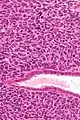

| Micrograph of a uterine adenosarcoma showing a mitotically active malignant stroma and benign glands. H&E stain. | |

Uterine adenosarcoma have, by definition, a malignant stroma and benign glandular elements. The World Health Organization (WHO) criteria have a mitotic rate cut point; however, this is often disregarded, as bland-appearing tumours with a low mitotic rate are known to metastasize occasionally.[2]